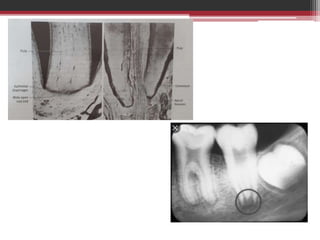

GENERAL ANATOMY

• Occupies centre of tooth – pulp

chamber & root canals

• Soft connective tissue

• Crown – coronal pulp

• Root – radicular pulp